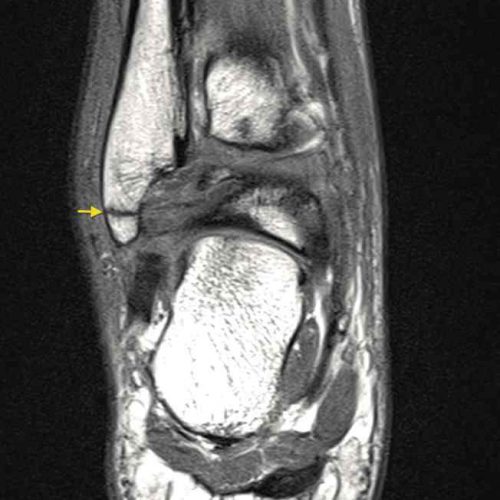

Fratura avulsão do maléolo lateral do tornozelo.

Corredora com história de entorse do tornozelo provocando dor, limitação funcional e inchaço articular.

Imagem de ressonância magnética (Cor T1) com identificação de fratura transversa do maléololateral da fíbula com desvio mínimo.